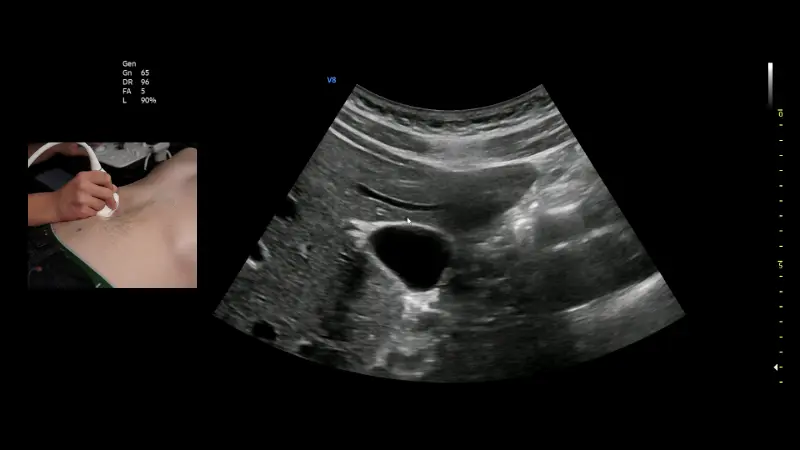

Inhalte sind wichtige allgemeine Grundlagen der Ultraschalldiagnostik und die Einführung in die sonografische Organdiagnostik in Akutsituationen (Herz, Thorax und Abdomen). Dieser Kurs bildet ebenfalls die Basis für die Zertifizierung Sonographie im Rettungsdienst.

In diesem Kurs werden systematisch Untersuchungs-techniken zur erweiterten sonografischen Organ-diagnostik (Herz, Thorax, Abdomen, Gefäße) in Akutsituationen mit den für Akutmediziner wichtigen Pathologien vermittelt.